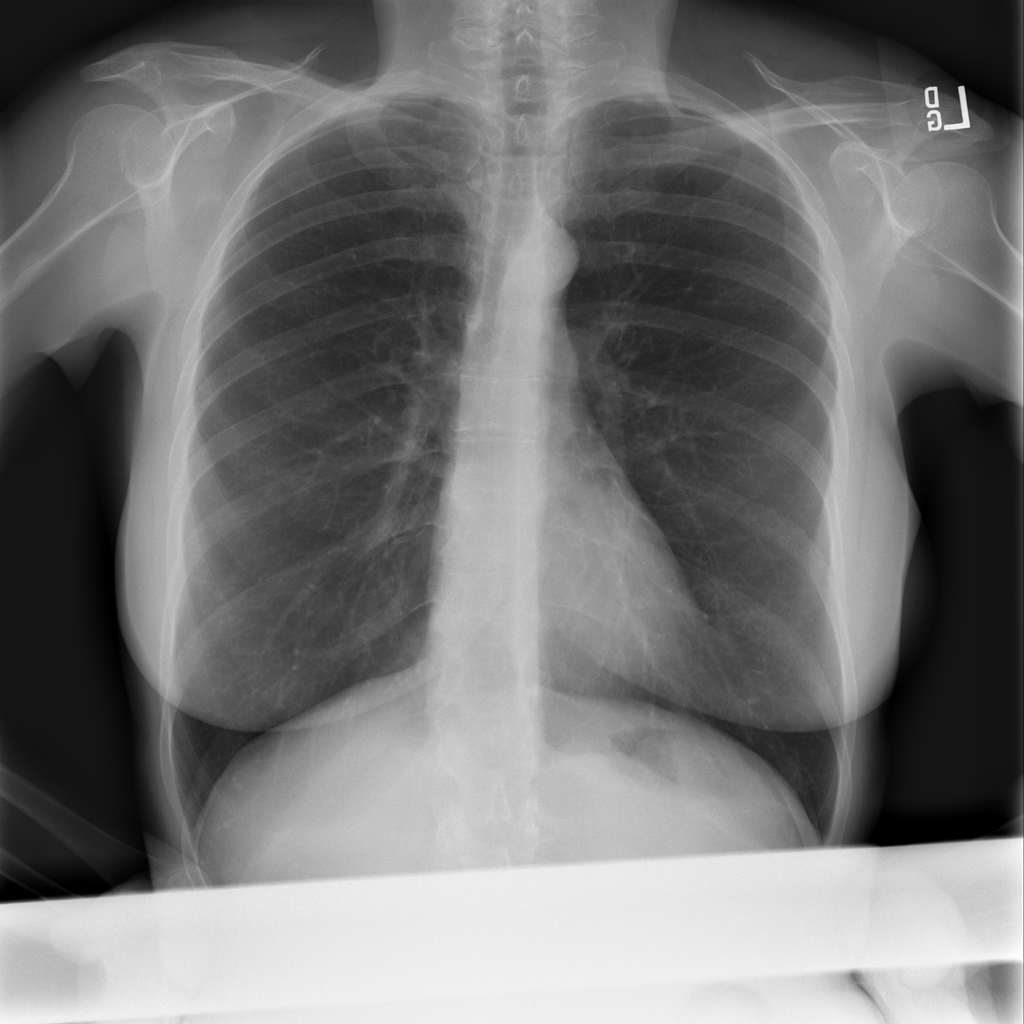

PAT-894B · IMG-000Emphysema

PAT-894B · IMG-000

PA